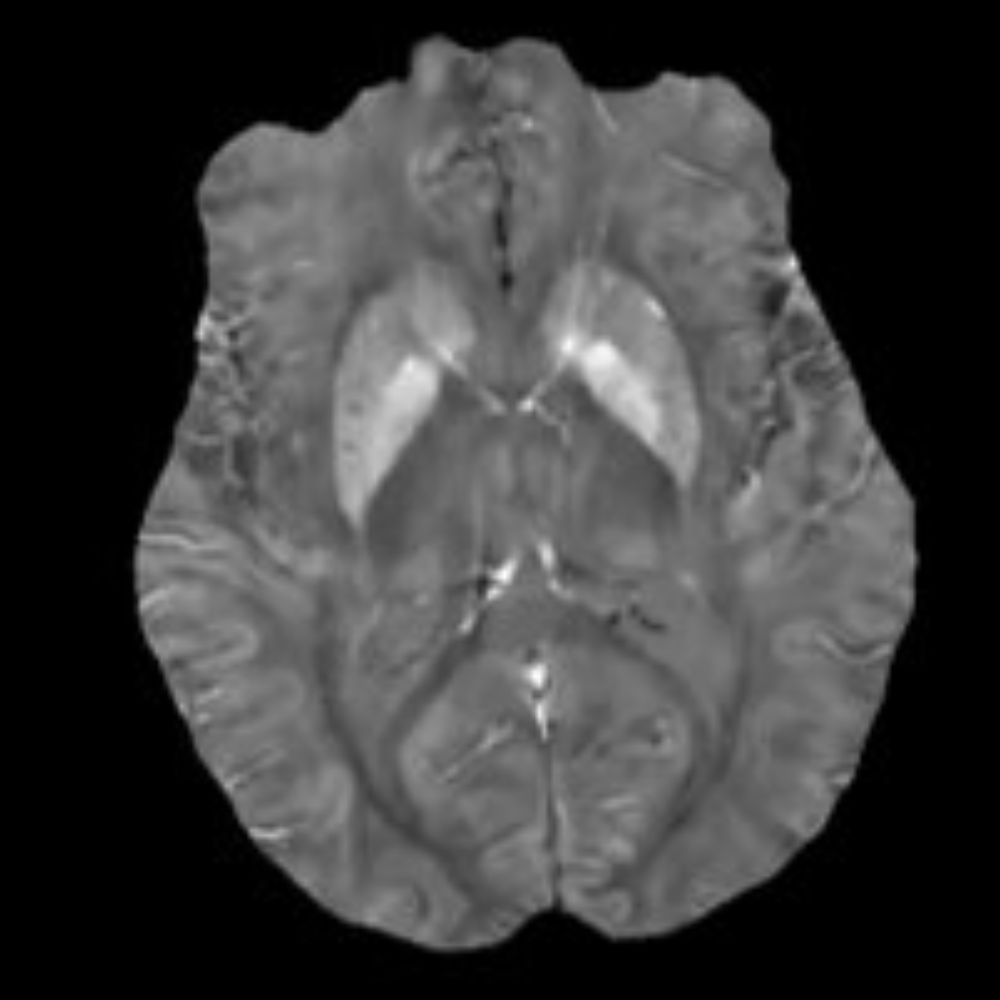

QSM4SENIOR: the gold standard for rusting brains

QSM4SENIOR: the gold standard for rusting brains Ventio and NeuroSpin are partners in a recently-selected project by the European Open Science Cloud in Life Sciences (EOSC-Life) to reveal an innovative early biomarker of pathological aging brain. Ventio engages in research … Read More